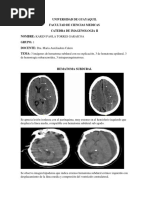

Hemorragia Subaracnoidea Aneurismtica

sacin de sangre proveniente de ruptura de un aneurisma cerebral en espacio subar

Puede extenderse e inundar: Cisterna basal Ventrculos Espacio subaracnoideo espinal.

La ruptura del aneurisma cerebral conduce a hemorragia subar

la ruptura de un aneurisma es la HIDROCEFALIA . aponamiento de vellosidades aracnoideas por productos derivados - lisis de elemen

gnstico : iante estudios seriados con TC Se observa: Responde a la administracin de diurticos osmticos Tamao creciente de ventrculos

ico: La ciruga consiste en: acin clnica Craneotoma dos de: Insercin de clip de plata especial se ajusta alrededor del cuello del an oTC (localizacin y magnitud) oPuncin lumbar (presencia de sangre en LCR) oAngiografa.